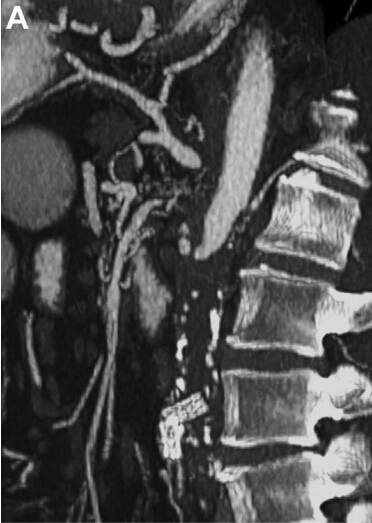

术后 CT 显示置入的血管清晰可见,且肠系膜上动脉充盈(图 C 和 D)。

图 C、D. 术后 CT 显示置入的血管清晰可见,且肠系膜上动脉充盈